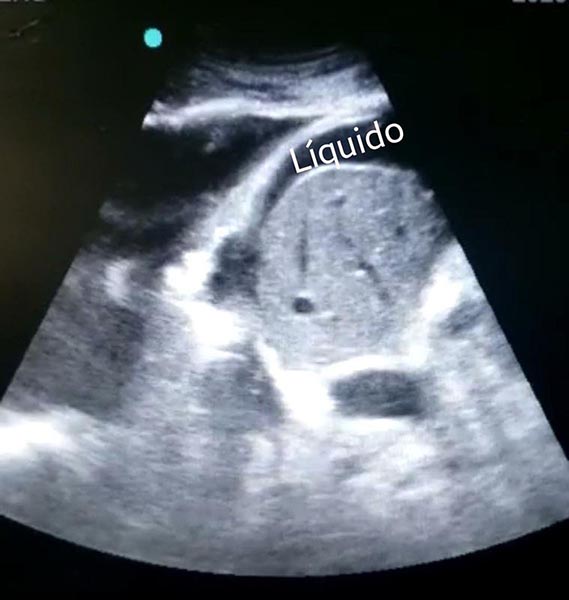

A imagem acima foi feita com um transdutor de baixa frequência, especificamente um probe convexo, na localização do espaço hepatorrenal, com o paciente na posição supina.

Podemos encontrar um conteúdo anecoico (preto) entre o parenquima hepático e a linha diafragmatica, provavelmente significando líquido ascitico.

Além disso, há derrame pleural, à esquerda do vídeo, também em preto, com achado adicional de consolidaçoes pulmonares em base direita.